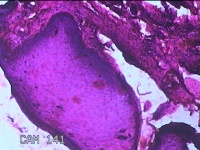

下唇肿物

性别

男

年龄

34岁

临床诊断

唇粘液囊肿

一般病史

下唇肿物2周。

标本名称

大体所见

灰白暗红色肿物0.7x0.5x0.3cm一个,表面光滑。